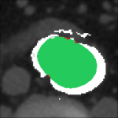

In Figure 12 we provide some examples of outputs to give a visual comparison. We have also included the DCI index, which is maybe the most intuitive for evaluating the performance of the two approaches.

| Patient | Basal | CM | DA | AI |

|---|---|---|---|---|

| P14 | ![]() |

![]() |

| DCI: | DCI: | |||

| P19 | ![]() |

| P20 | ![]() |

| P22 | ![]() |

| P26 | ![]() |

| P30 | ![]() |

| DCI: | DCI: |

We notice that, both approaches demonstrate effective performance. The output from the deterministic approach (DA) is clear, with regular contours of the patent lumen, in contrast to the AI approach output, which exhibits blurriness and more realistic contours. Occasional instances of bad performances in both approaches may be attributed to the complexity of the morphology of individual slices. Nonetheless, the overall quality of predictions is deemed satisfactory.